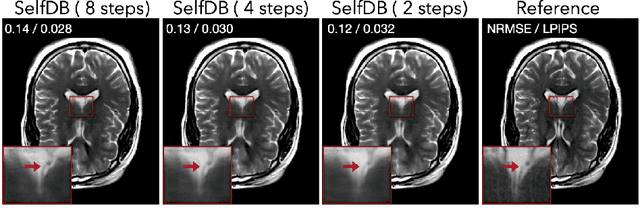

Abstract:Diffusion bridges (DBs) are a class of diffusion models that enable faster sampling by interpolating between two paired image distributions. Training traditional DBs for image reconstruction requires high-quality reference images, which limits their applicability to settings where such references are unavailable. We propose SelfDB as a novel self-supervised method for training DBs directly on available noisy measurements without any high-quality reference images. SelfDB formulates the diffusion process by further sub-sampling the available measurements two additional times and training a neural network to reverse the corresponding degradation process by using the available measurements as the training targets. We validate SelfDB on compressed sensing MRI, showing its superior performance compared to the denoising diffusion models.